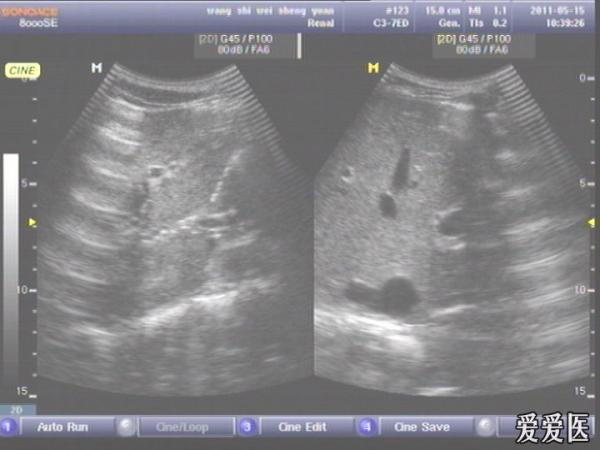

患者,男,38岁,进食后突发上腹部持续性剧烈疼痛一小时来查。超声见横膈与肝之间、上腹部皮下气体强反射回声,后伴多重反射,肝前、肝肾间隙,腹腔肠管间均可见游离无回声区。直视腹部见上腹部似板样。结合病史提示“胃肠道穿孔”。急诊手术证实。

左肝外叶的那个切面如果能看到气体回声的话,那就应该高度怀疑这个病了。好切面,好好学习,太有用了,楼主辛苦感谢感谢。